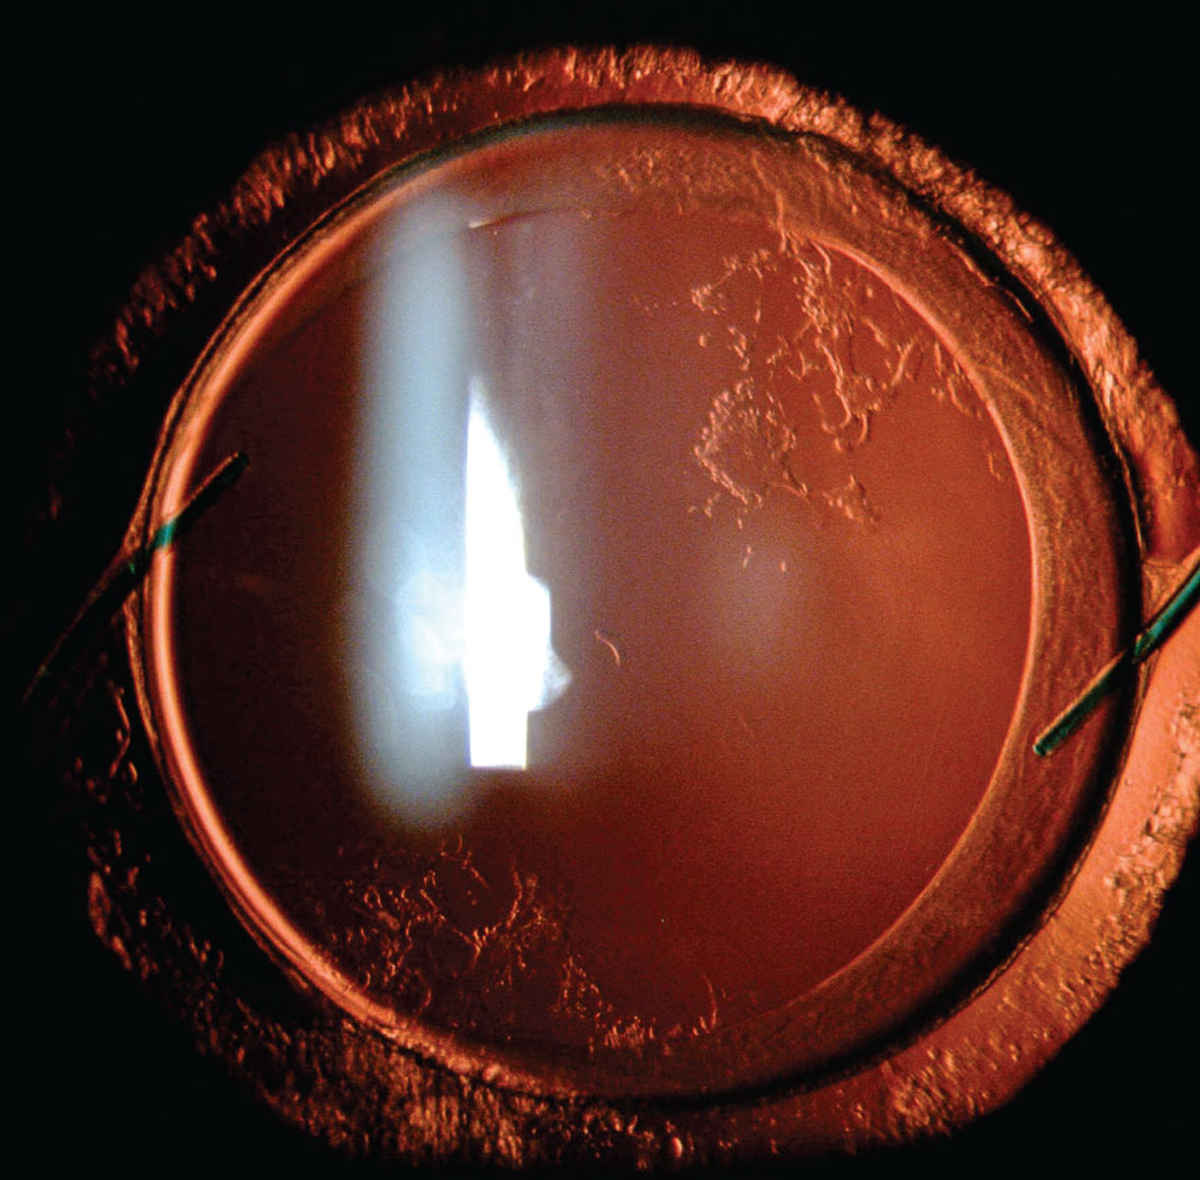

"That's Heavy, Doc" — An elderly patient presents with visual complaints and oculomotor findings. What might be the cause?